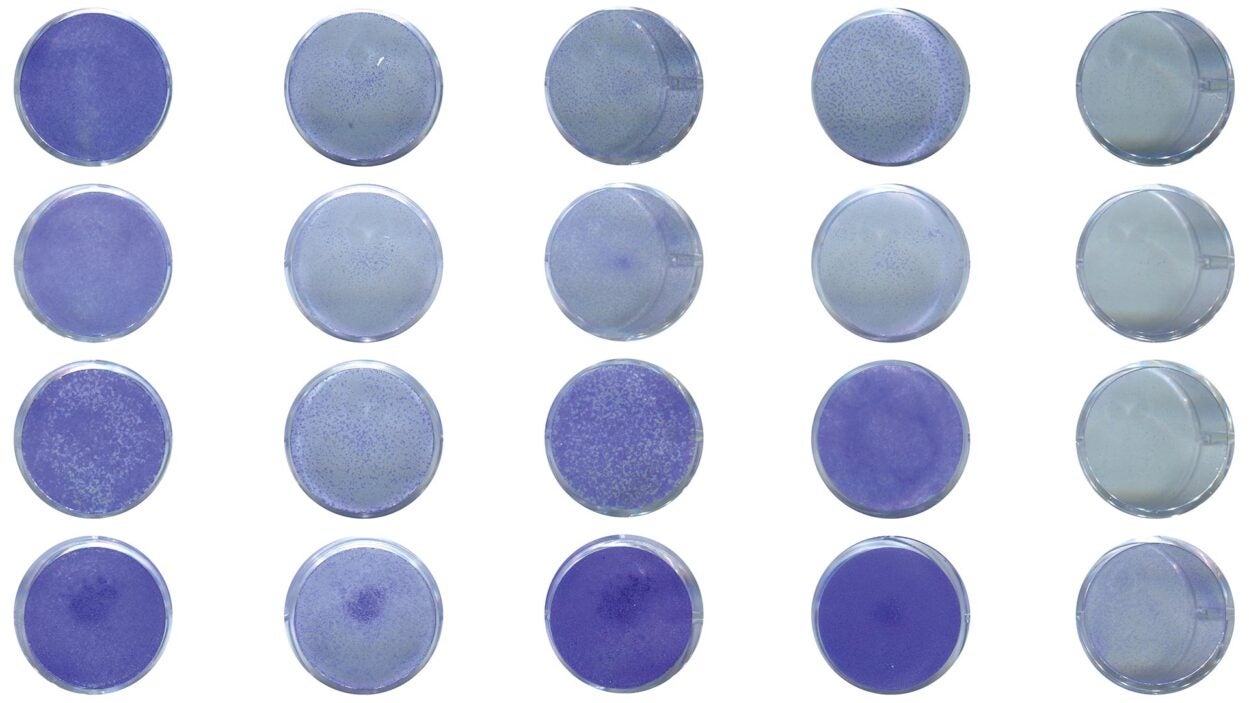

Speckles sound innocent enough, like little spots. But don’t be fooled. These tiny structures could someday have big implications for cancer care. Listen to the podcast »

What are nuclear speckles and how might these mysterious structures impact your DNA? Get an inside look from CSHL Assistant Professor Kate Alexander. Watch the video »

Research from new CSHL Assistant Professor Katherine Alexander suggests that nuclear speckles could influence kidney cancer patient outcomes. Read the story »

Her team will explore mysterious cellular structures known as nuclear speckles and their role in diseases such as cancer. Read the story »